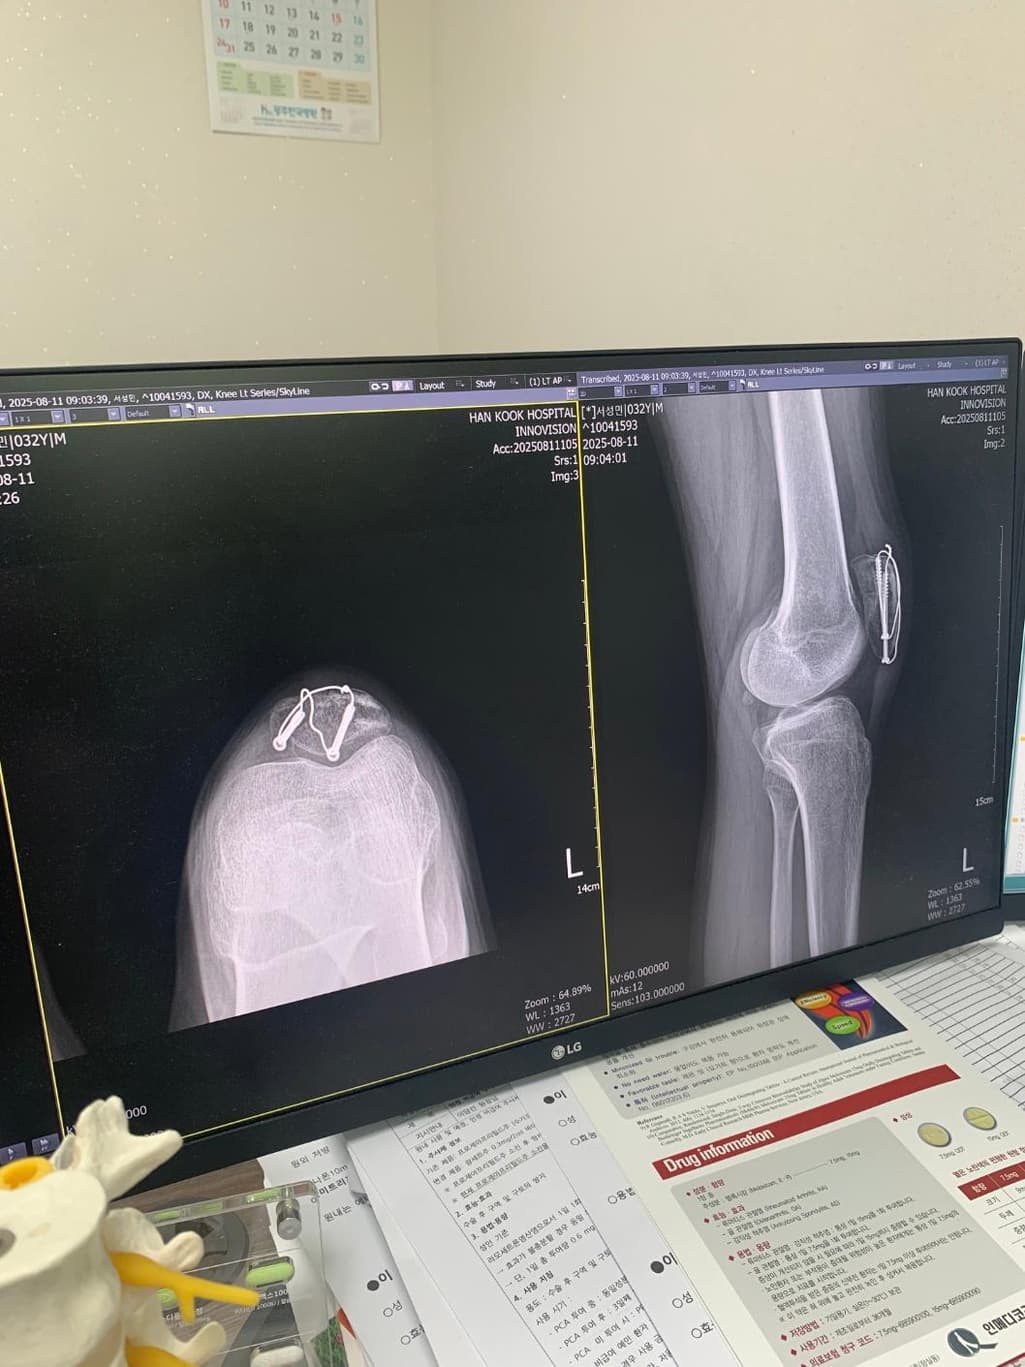

슬개골 골절 수술후 질문좀 드리겠습니다

슬개골골절 수술후 8주차 엑스레이입니다 질문좀드릴게여ㅠㅠ

1. 엑스레이상 유합이 잘되고있는건가요?

2. 수술부위를만져보면 한쪽부분이 골절선처럼 움푹파여서 보여지는데 혹시 뼈가 생기다가 만걸까요?

현재로썬 엑스레이상 유합이 잘되고있는것으로 보여지지만 다방면으로 확인이 필요한 부분이기에 전문의에 소견을 들어보시길 바랍니다.

보통 수술 후 봉합 부위에선 연부조직의 변화로 울퉁불퉁한 느낌이 들 수 있으며, 뼈가 생기다만것은 아니니 걱정하지않으셔도 됩니다.

엑스레이 상에서는 대체로 골절 부위가 붙어가는 양상이 보이는경우가 많으나 정확한 유합 여부는 담당 의사의 판독이 필요합니다.

수술 부위가 움푹 패여 만져지는 것은 뼈 모양이 완전히 매끄럽게 회복되지 않았거나 금속 고정물 주위 변화일 수 있습니다.

뼈가 생기다 만 것이라기 보다는 회복 과정에서 생긴 모양 차이일 가능성이 큽니다! 걱정된다면 다음 외래에서 촬영한 엑스레이와 촉진 소견을 함께 보여주고 확인하는 것이 가장 안전합니다!

사진상으로는 수술 이후 금속고정물이 자리를 잡고 골 유합이 이루어지고 있는 것으로 보이는데요, 통증이나 불편감이 심하지 않고 특별히 다른 소견이 없으셨다면 회복이 잘 진행되고 있는 것으로 생각됩니다.

표면의 변화는 뼈의 회복과정에서 일어날 수 있는 표면 변화로 생각됩니다.